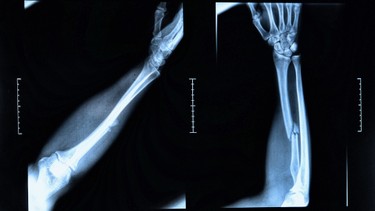

/x_quang_xuong_cang_tay_chi_dinh_quy_trinh_va_luu_y_an_toan_1_e256cf24e3.jpg)